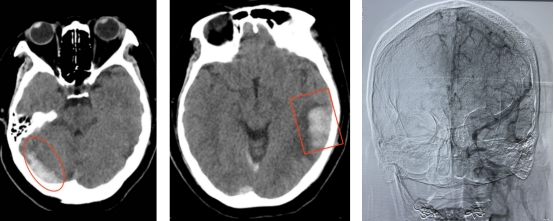

术前影像

静脉血栓影 静脉性脑出血 静脉窦广泛血栓

患者转入神经内科后,行腰穿及核磁共振检查,考虑患者颅内静脉窦广泛血栓形成,病情危重。患者有行颅内静脉窦造影及取栓指征,与患者家属商议后,第一时间脑血管造影,明确颅内静脉窦血栓,并给与颅内静脉窦取栓,5小时后患者静脉窦再通,成功回病房进一步抗凝药物治疗。